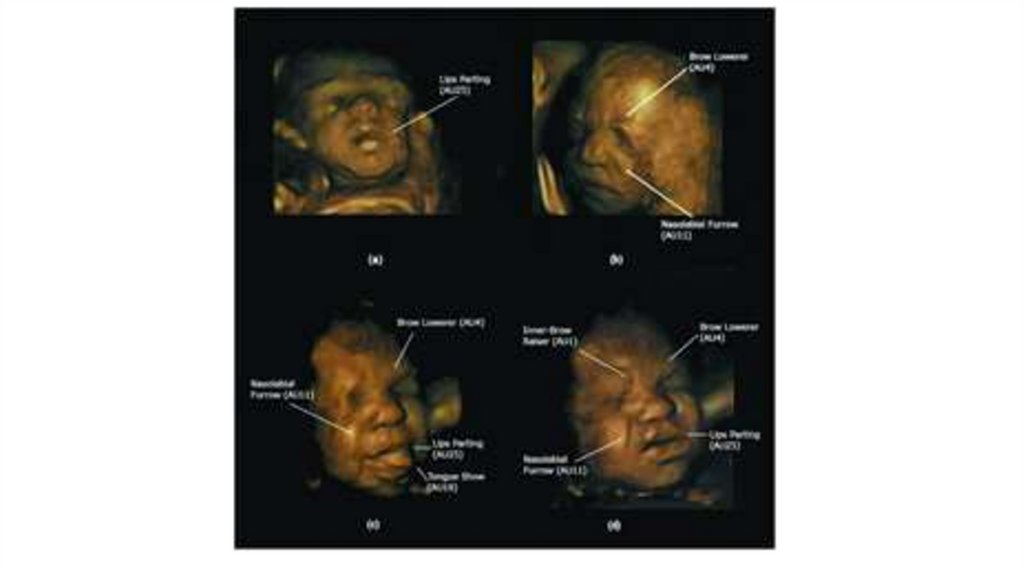

19. Проявление эмоций в жестах, мимике, позе.